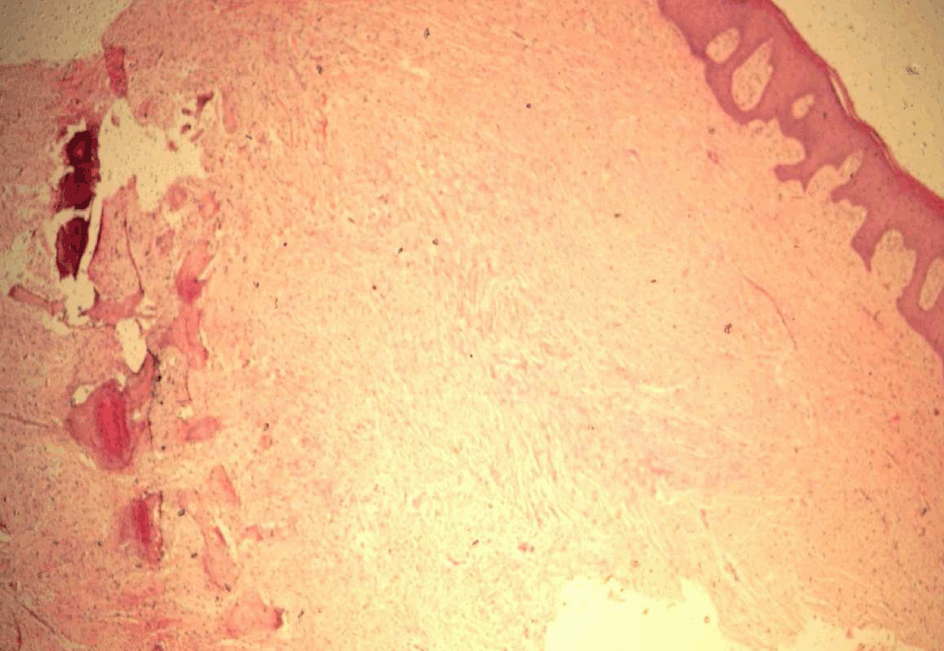

A 25-year-old male patient reported to the outpatient department with a slow-growing painless growth that had been present labially in the left incisor-canine region. The lesion started as a small nodule approximately three years earlier. Examination revealed an approximately 1 cm × 1 cm pedunculated, non-tender, firm, pinkish red growth present on the labial gingiva in relation to the maxillary left central incisor and canine (figure 1). Radiographic examination revealed no significant change in the underlying normal bone architecture The patient's past dental and medical histories were non-contributory. Excisional biopsy was performed. The differential diagnosis included traumatic fibroma and pyogenic granuloma. H&E stained sections shows parakeratinized stratified squamous epithelium and dense fibrous connective tissue stroma. The connective tissue showed dense bundles of collagen fibres (figure 2). Deep in the connective tissue were seen numerous ossifications in the form of bony trabeculae (figure 3). The fibroblasts were plump and active around ossifications.

Figure 2: Photomicrograph showing parakeratinized stratified squamous epithelium, cellular fibrous connective tissue stroma with bony trabeculae. (H&E, x100).